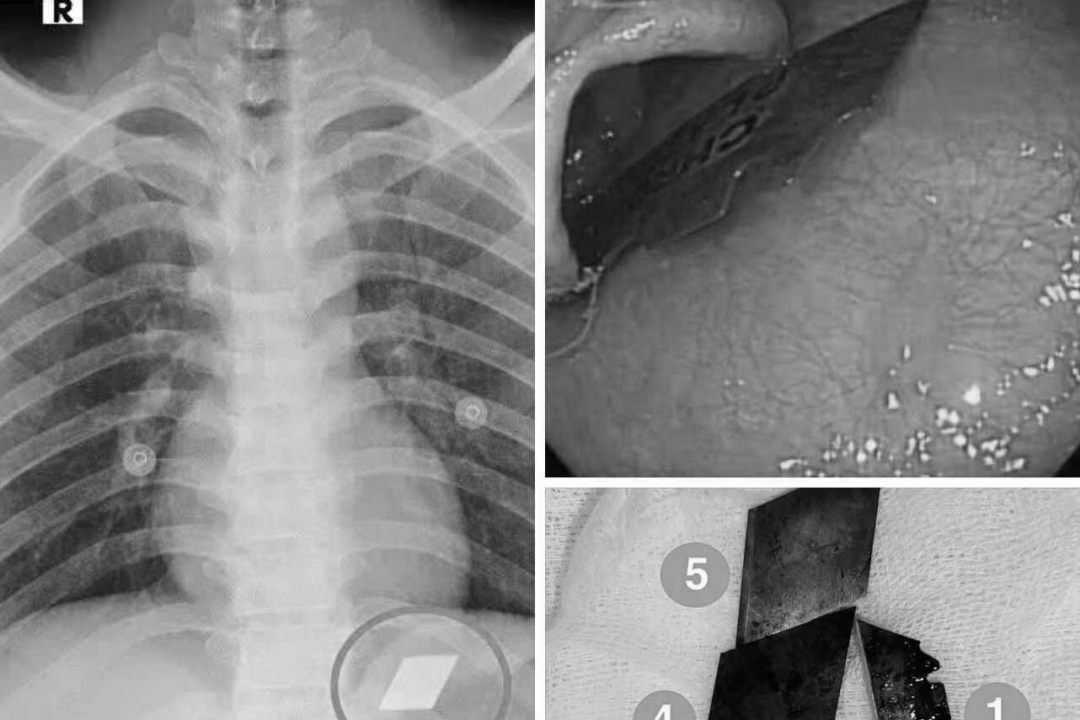

Ngày 10/7, Khoa Hồi sức cấp cứu – Bệnh viện Đa khoa Bình Dương đã tiếp nhận một trường hợp cấp cứu hiếm gặp. Bệnh nhân P.V.L, 26 tuổi, được đưa vào viện sau khi nuốt nhiều dị vật kim loại sắc nhọn, bao gồm dao rọc giấy và dao lam.

Qua thăm khám và chụp X-quang, các bác sĩ phát hiện các dị vật cản quang tại vị trí dạ dày. Ngay lập tức, bệnh nhân được chỉ định nội soi cấp cứu để gắp bỏ dị vật. Với sự phối hợp chặt chẽ giữa ê-kíp nội soi và gây mê, các bác sĩ đã thành công gắp 4 lưỡi dao rọc giấy ra khỏi dạ dày và một phần lưỡi dao lam mắc tại vùng hạ họng – miệng thực quản.

Sau thủ thuật, bệnh nhân được theo dõi sát và đã ổn định sức khỏe, xuất viện trong tình trạng an toàn. Theo bác sĩ Phan Lê Quốc Du, Khoa Thăm dò chức năng, Bệnh viện Đa khoa Bình Dương, các dị vật sắc nhọn trong đường tiêu hóa đòi hỏi phải can thiệp nội soi kịp thời. Nếu không lấy ra kịp thời, dị vật có thể gây thủng thực quản, thủng ruột, dẫn đến biến chứng nặng nề, thậm chí tử vong.